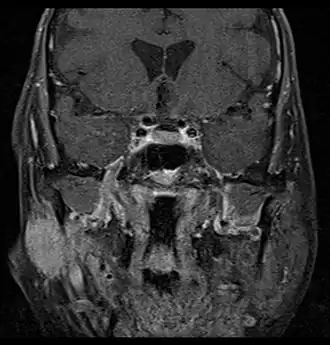

Radiograficamente, o CAC se assemelha a outros tumores malignos, tendo aspecto hiperintenso na ressonância magnética em T1.[1] Ele possui uma característica importante que pode ser visualizada com o seu crescimento nos exames de imagem, a invasão perineural: as células tumorais envolvem completamente o feixe nervoso dentro do tumor, aproveitando o trajeto do nervo para se espalhar para outras áreas.[1]

O tratamento consiste na ressecção cirúrgica completa com margens livres, e a maior parte dos pacientes recebe radioterapia adjuvante pelo alto risco de recidiva local e a sobrevida a longo prazo baixa.[1] Considerando que a remoção do tumor é difícil pelo seu crescimento descontínuo, graças à invasão perineural, ilhotas tumorais podem existir sem conexão com a massa tumoral principal, e o uso da ressonância magnética é recomendado para analisar o trajeto dos nervos até a base do crânio.[2] A quimioterapia é normalmente reservada para pacientes com metástase.[1] Para os pacientes com tumores inoperáveis, recidivantes ou com doença residual após cirurgia, a radioterapia é considerada o tratamento mais eficaz.[23][24][25][26]